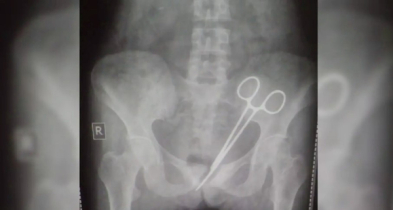

ভারতে নারীর পেটে কাঁচি রেখেই সেলাই, ১ যুগ পর বের করলেন চিকিৎসক

পেটের ব্যথা নিয়ে হাসপাতালে গিয়েছিলেন এক নারী। চিকিৎসক জানান ব্যথার কারণ অ্যাপেন্ডিক্স। পরে অস্ত্রোপচারের মাধ্যমে অ্যাপেন্ডিক্স অপসারণ করা হয়। কিন্তু বাসায় ফেরার পর আবারও বাড়তে শুরু করে ব্যথা। এই ব্যথা নিয়েই এক যুগ ধরে বিভিন্ন হাসপাতালে চিকিৎসকদের